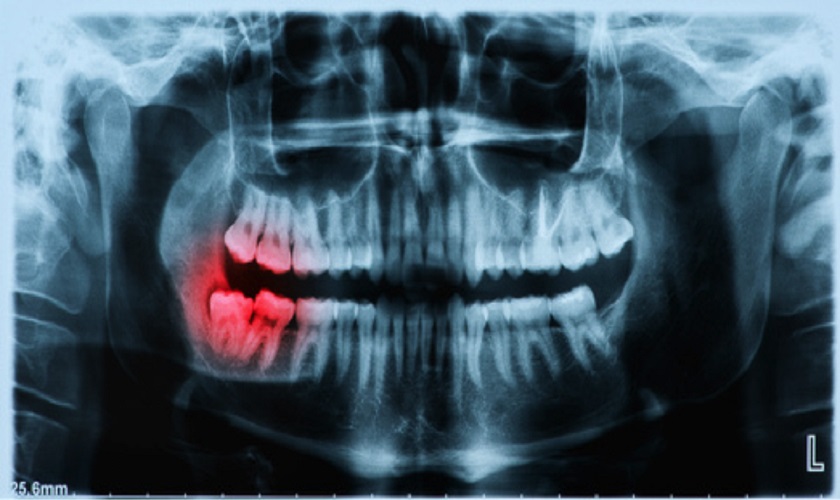

Trước khi nhổ răng số 8, bạn cần tiến hành chụp X – quang, xét nghiệm máu,… để bác sĩ nắm được mức độ phức tạp, tình trạng răng một cách cụ thể cũng như tránh các rủi ro do các vấn đề về đông máu,…

Cần tiến hành chụp X – quang trước khi nhổ răng khôn